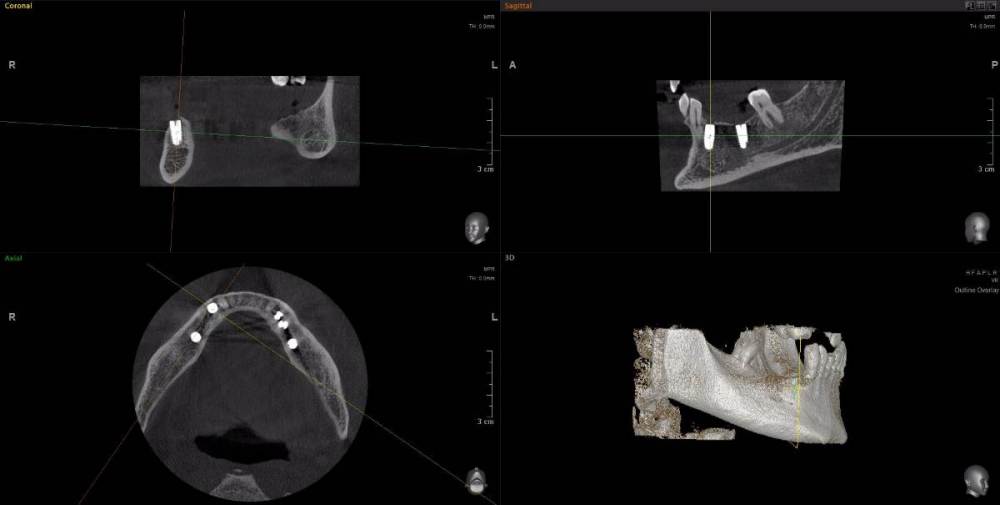

m-art-a23 Опубликовано 21 апреля, 2021 Поделиться Опубликовано 21 апреля, 2021 Здравствуйте. Два дня назад мужу установили 5 имплантов Ankylos на нижнюю челюсть (2+3). Спустя 30-40 мин после операции появилась сильная острая боль, которая не уменьшается по настоящее время. Боль похожа по ощущениям на пульпитную, не снимается никакими НПВС, кроме кеторолака. А/б, А/гистаминные, холод местно, хлоргексидин - все рекомендации выполнялись. На осмотре врачом не обнаружено следов воспаления, КТ сделал - без особенностей. Что может служить причиной такой боли, сколько она может длиться и что делать в данной ситуации? Врач-имплантолог ничего внятного не предложил. Ссылка на КТhttps://cloud.mail.ru/public/EvKn/ULqxLy6BD Ссылка на комментарий

red_butler Опубликовано 22 апреля, 2021 Поделиться Опубликовано 22 апреля, 2021 7 минут назад, m-art-a23 сказал: Нет, не один. Но он лучший. Скажите пожалуйста, что служит причиной боли, по-Вашему? Неужели все импланты нужно убирать только по Кт трудно судить, но есть вопросы по позиционированию имплантов... боль может быть вызвана перегревом кости во время формирования ложа импланта, но в этом случае она появляется примерно с третьего дня. Так же боль может вызывать гиперкомпрессия импланта, и может болеть кость если ее придавили формирователем десны. Я бы обсудил с хирургом удаление среднего импланта слева 1 Ссылка на комментарий

Irouil Опубликовано 22 апреля, 2021 Поделиться Опубликовано 22 апреля, 2021 Я бы рекомендовал удаление среднего импланта слева, независимо от наличия/отсутствия болевых ощущений боль может быть признаком каких-то описанных моим коллегой процессов, а может ничего кроме самой боли не означать (менее вероятно, но и такое бывает). Если удаление упомянутого импланта поможет против болевого синдрома - это win-win если хирург не видит необходимости удаления импланта, я бы рекомендовал сходить на осмотр к ортопеду, который будет в будущем эти импланты протезировать. Возможно у него найдутся весомые аргументы для коллеги 3 Ссылка на комментарий

Irouil Опубликовано 22 апреля, 2021 Поделиться Опубликовано 22 апреля, 2021 (изменено) 1 час назад, m-art-a23 сказал: Благогдарю за совет. Если Вам не трудно, объясните пожалуйста, что не так со средним имплантом. Описанные процессы, если таковые имеют место быть, должны постепенно прийти в норму? Другими словами, сколько еще нужно времени, чтобы окончательно принять решение об удалении импланта (имплантов)? Сегодня третьи сутки после установки. Боль сохраняется. Средний имплант расположен чрезвычайно близко к соседнему, расположенному кпереди от него. С очень большой долей вероятности это может привести к значительной резорбции (убыли) костной ткани между ними, что для любых имплантов очень вредно, а для конкретно Анкилосов - губительно из-за особенностей их протезирования. Если неблаготворные процессы (компрессионный или термический некроз) присутствуют, то импланты просто не интегрируются (не приживутся) - те, что зашиты не выдержат нагрузки при раскрытии, а тот, на котором стоит ФДМ - расшатается через 2-3 недели. Это не призыв проверять его стабильность языком, сейчас его лишний раз лучше не трогать. В норме после имплантации боли держатся 1-2 дня, если все не очень хорошо - держатся 2-3 недели, но даже в таком случае имплант может интегрироваться, поэтому решение об его удалении в таком случае должно, по моему убеждению, быть совместным между врачом и пациентом, и приниматься в индивидуальном порядке Изменено 22 апреля, 2021 пользователем Irouil Ссылка на комментарий